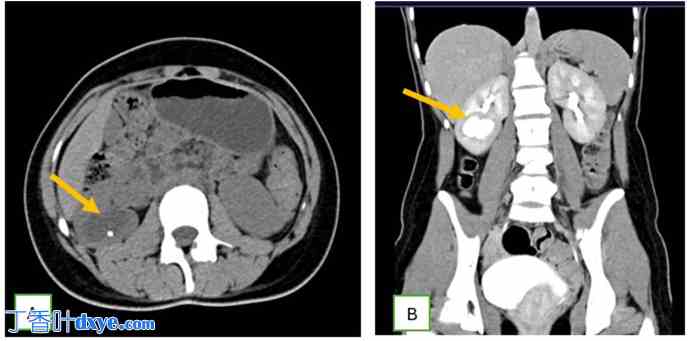

图1.

超声检查显示右肾中盏(箭头所示)内有结石(十字交叉状),该结石扩张,并有狭窄通道,与肾门处类似囊肿。